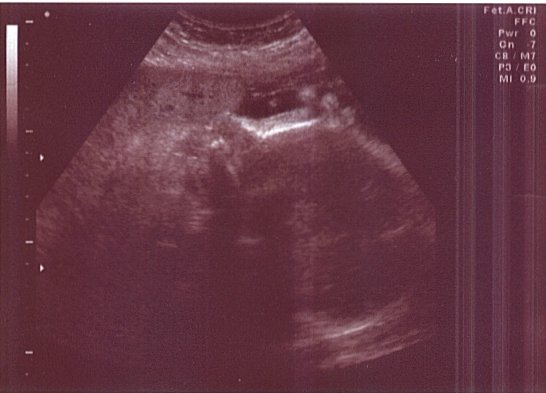

This is a profile shot of baby Harrell. Interestingly enough it gets harder to get good images and look at internal organs as the baby develops. Skeletal structures interfere with the ultrasound. This was taken on June 17, 2004.